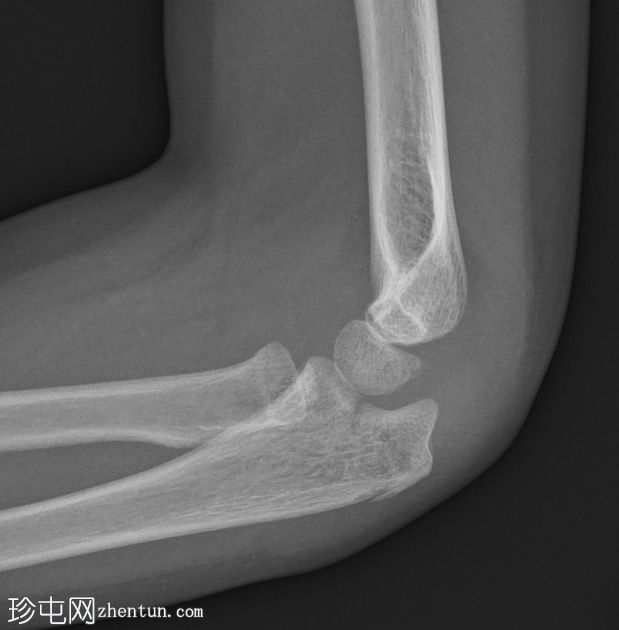

侧位片

可见鹰嘴关节内骨折,桡骨颈轻度移位骨折,侧位片可见轻微硬化。肘关节对位良好。关节积液,表现为前后脂肪垫抬高。

儿科,桡骨颈骨折比桡骨头骨折更常见(与成人相反)。如本例所示,桡骨颈骨折通常表现隐匿,轻微硬化或轻度成角可能是唯一的体征。

鹰嘴骨折虽然不常见,但容易被忽略,因此是常见的漏诊骨折。侧位片通常最有帮助。